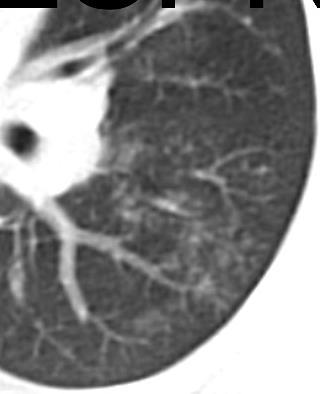

Early: "Halo" sign

Imaging of Covid 19 infection in children

Local infection Surr vasc congestion

Apicale sinistraa Medio -Basale sinistra

Basale sinistra Basale sinistra